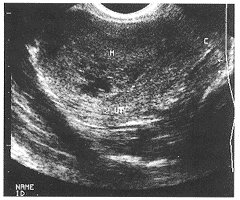

经阴道超声对宫内残留胎物的诊断价值